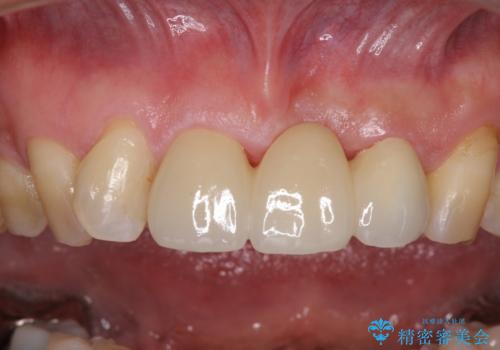

- 保険診療の前歯のブリッジが、形態も色も不自然で気になるとのことで来院された患者様です。

神経の抜かれている土台の歯は根管治療を行った上で、オールセラミックブリッジにより補綴することとしました。

術前の状態より、欠損部位には歯肉移植術が必要と思われましたが、仮歯で調整したところ自然な歯列となったため、外科処置は行わずに自然な口元に仕上がりました。